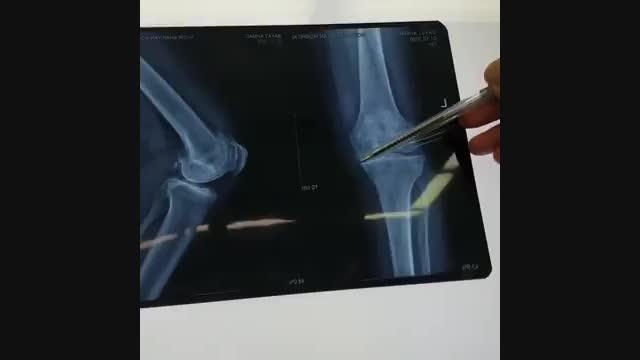

تعویض مفصل زانو در سن بالا

دکتر هومن جولایی جراح ارتوپد در جراحی تعویض مفصل زانو و لگن ، آرتروسکوپی و سایر بیماری های ستون فقرات تبحر بالایی دارند. جهت مشاوره با ایشان با شماره های 09308100510-02636563602 تماس حاصل فرمایید. آدرس سایت: dr-joulaei.com آدرس اینستاگرام: https://www.instagram.com/drhoomanjoulaei/